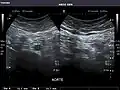

Aorta: Visualized portions normal in caliber, 16 x 15 mm.